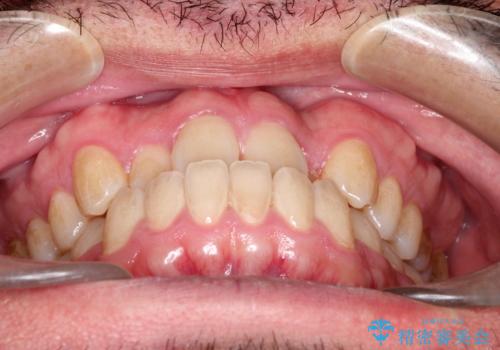

前歯が反対にかんでいる インビザラインとワイヤーを組み合わせた矯正治療

- 前歯が正常とは反対にかんでいるとのことで、来院されました。

患者様がマウスピースを希望されていましたが、上の前歯のがたつきを先にワイヤーで改善する方が早く治療が終了することが可能であるとお伝えし、上顎のみ半年間ワイヤーで治療を行いました。

マウスピースのみでの治療も可能でしたが、治療期間がもう少し延長していた可能性があります。